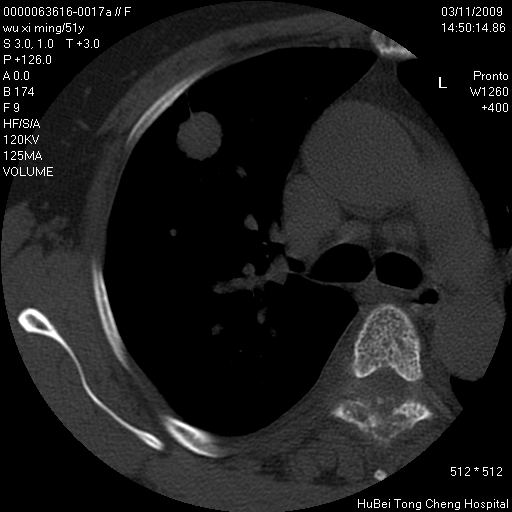

患者 女,51岁。因“胆囊炎,胆囊结石”,行常规术前胸部x线检查发现:右上肺结节病灶,建议行进一步检查。患者无咳嗽、咳痰及咯血等呼吸道症状,近期出现背部疼痛不适。

胸部ct轴位平扫(层厚10mm,螺距1.5,重建间隔10mm;部分层面:层厚3mm,螺距1.0,重建间隔3mm),图像如下:

1、周围型肺癌。(毛刺正、血管束集征,分叶。)

集束征,胸膜牽拉征,毛刺,淺分葉高度提示ca.

右肺周围型肺癌伴肺内转移及胸椎转移。已无手术机会。